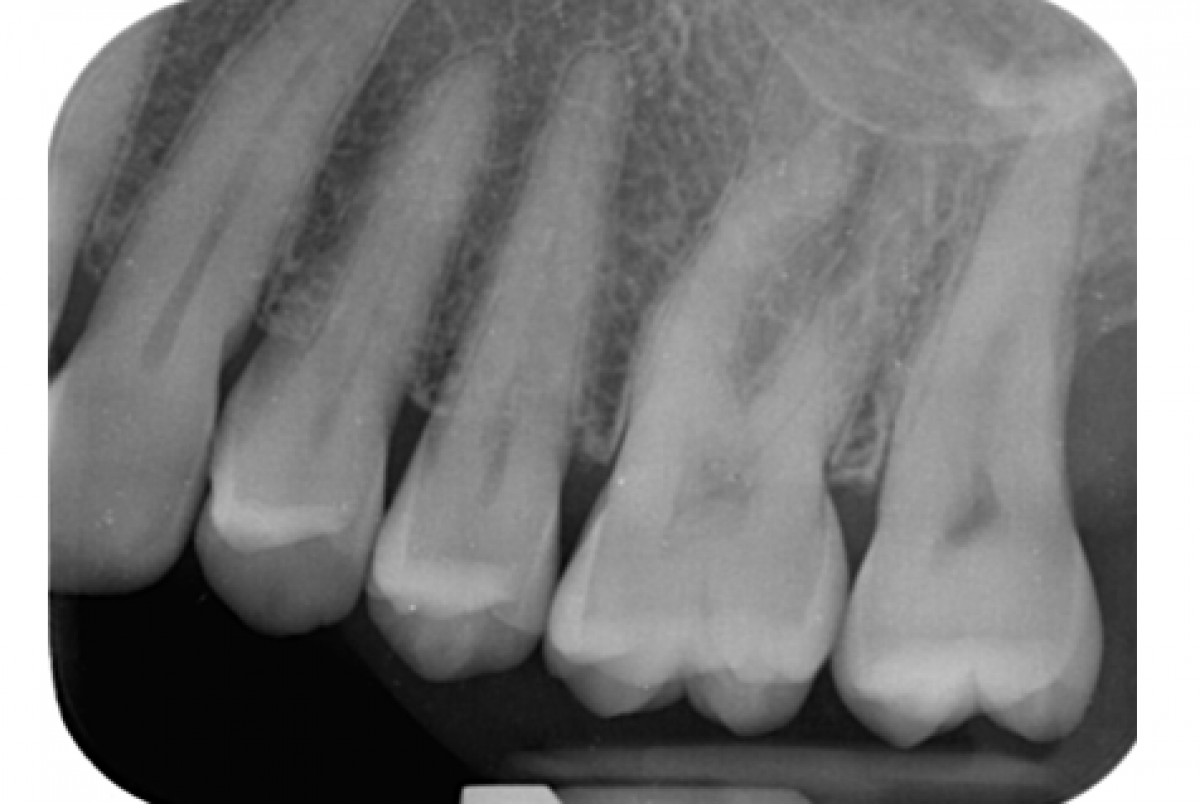

The intraoral periapical examination (Fig. 1) reveals bone resorption at the distal root of element 2.7. The periodontal examination shows probing on the distal side and the vestibular side, with exudate.